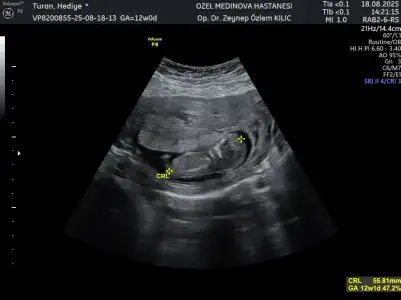

Hafta olarak 12+1 doktor net olarak söylemesede kız bebek gibi duruyor dedi hayırlısı olsun inşallah teşekkür ederim

• 1000024108.webp

1000024108.webp

27,8 KB · Görüntüleme: 24